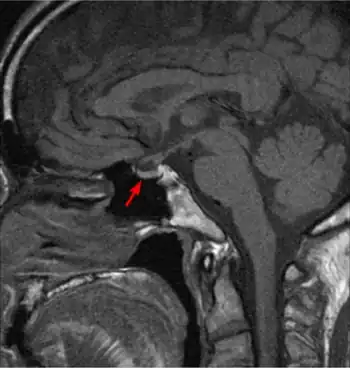

Familial Dysalbuminemic Hyperthyroxinemia - MRI of pituitary shows no pituitary gland tumor